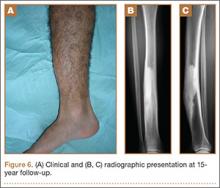

At the last follow-up 15 years after surgery, the anterior tibial bowing was not changed (Figure 6A), but the patient additionally complained of skin irritation after intense training wearing boots during military service. The radiographic appearance of the lesion was also not changed, while the periphery of the lesion exhibited scarce radiating bony streaks with rounded contours (Figures 6B, 6C). The clinical symptoms and signs from wearing military boots completely subsided after a couple of weeks’ rest from daily army activities, but the mild spontaneous pain and the local tenderness over the tibial bowing persisted.